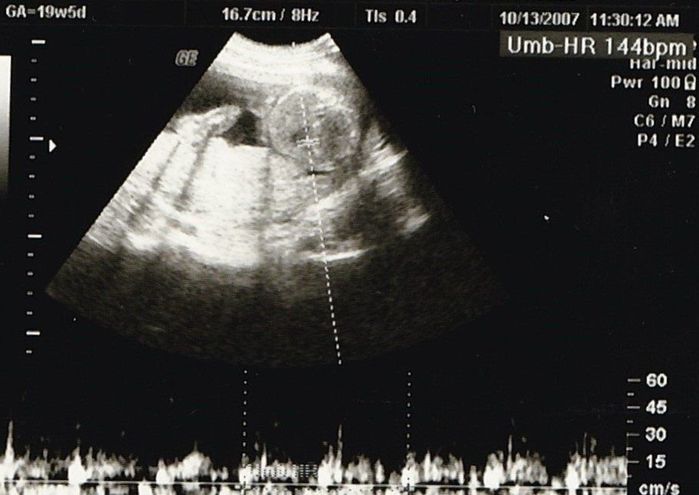

妊娠19週目のエコー写真

安定期に入り、検診のたびに体重や血圧を測るようになりました。前回の検診時から、8~10kgの増加が目安と言われていましたが、妊娠15週から19週の間ですでに1.3kg増。強い食欲と眠気に勝てない毎日に危機感が募り、マタニティーヨガ、マタニティービクスを開始しました。